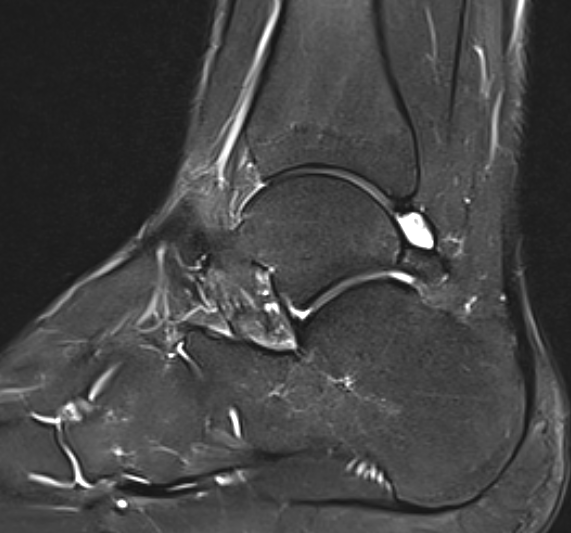

MRI

Findings

- synovitis over posterolateral process talus

- fluid in sheath about FHL

- edema around os trigonum

- edema posterior tibia bone

- thickened posterior capsule

Os trigonum FHL tenosynovitis with posterior ankle joint soft tissue

Stieda's process with ankle joint effusion